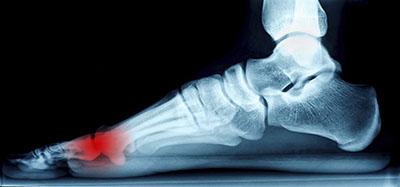

The feet serve as the foundation of the body. When pain is experienced, it’s therefore extremely important to identify early on what and where the issue is. The causes of foot pain vary greatly, including but not limited to diseases, deformities, improper footwear,...